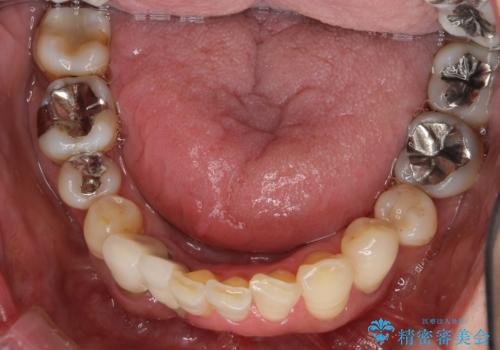

歯周病 インプラントによる咬合機能回復

- 歯が全体的にグラグラし、しっかりと物が噛めなくなり歯周病治療を希望され来院されました。

残すことのできる歯、残すことのできない歯を初期治療を進めながら見極め、最終的に臼歯部はインプラント、上顎前歯は入れ歯による補綴計画となりました。